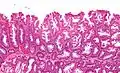

| Micrograph of a sessile serrated lesion. H&E stain. | |

SSLs are diagnosed by their microscopic appearance; histomorphologically, they are characterized by (1) basal dilation of the crypts, (2) basal crypt serration, (3) crypts that run horizontal to the basement membrane (horizontal crypts), and (4) crypt branching. The most common of these features is basal dilation of the crypts.

Unlike conventional colonic adenomas (e.g. tubular adenoma, villous adenoma), they do not (typically) have nuclear changes (nuclear hyperchromatism, nuclear crowding, elliptical/cigar-shaped nuclei).